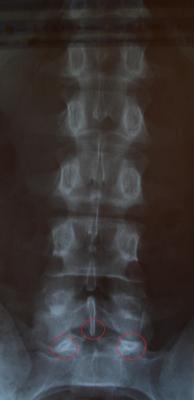

ich bin gerade von Prof. v. Torklus zurück. Er war sehr nett und hat sich viel Zeit für mich genommen. Sollange hat sich noch nie ein Arzt meine Röntgenbilder angeguckt. Was er mir dann sagte war jedoch nicht so schön.

Mein Problem sind die im Bild eingezeichneten Stellen. Zum einen ist der Dornfortsatz am unteren Lendewirbel deutlich zu lang. Zum anderen gibt es zwischen Lendenwirbelsäule und Steiß eine Verwachsung. Eine Art zusätzlichen halben Wirbel der da nicht hingehört. Alles ist angeboren und man kann im Gurnde nichts dagegen machen. Dann wurde mir ertsmal Blut abgenommen um zu gucken ob eine Entzündung vorliegt. Mein nächster Termin ist am Freitag.

Was mich wundert ist, dass es bisher keinem Arzt aufgefallen ist! Ich denke das kann man von jedem Orthopäden erwarten.

Dateianhänge

Problem.jpg

Problem.jpg (6.75 KiB) 9234 mal betrachtet

Das was Prof. v. Torklus auf dem RöBi eingekringelt hat IST tatsächlich M.Baastrup!

mal sehen was er Dir als Therapie vorschlägt. Den Halbwirbel seh ich auf Deinen Röbis beim besten Willen nicht!

das Wort Halbwirbel hat Prof. v. Torklus nicht benutzt. Er sagte, dass da eine Verwachsung(?)zwischen L5 und S1 ist. Und hat mir diese beiden weißen Stellen auf dem Bild gezeigt, die da nicht hingehören. Als ich ihm gesagt habe, dass ich mir das schlecht vorstellen kann hat er gesagt, dass man sich das so vorstellen könnte, dass da sowas wie ein zusätzlicher halber Wirbel ist. Vielleicht habe ich es auch falsch verstanden.

Ich ließ mir auch nochmal genau erklären und am Modell zeigen, wie es denn jetzt da unten genau aussieht. und zwar sind die Querfortsätze von L5 mit dem Kreuzbein verwachsen. Das ist in den beiden äußeren Kreisen auf dem Röntgenbild zu sehen. AUßerdem ist der Dornfortsatz von L5 zu lang. Dieser ragt durch ein Loch im Kreuzbein auf die darunterliegenden Nervenbahnen. Damit lassen sich die Dauerschmerzen und die starken Schmerzen beim Vorneüberbeugen erklären.